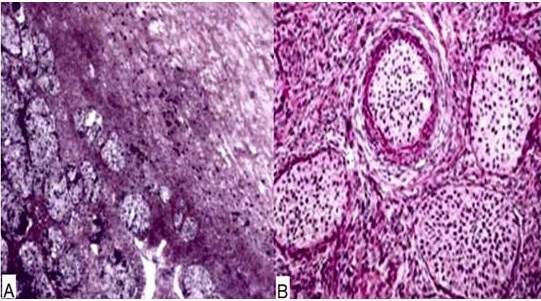

El examen macroscópico reveló tumor solido-quístico de 10 cm x 8 cm de diámetro, pálido, de color blanco-grisáceo con un área quística de 5 cm. La pared del quiste estaba engrosada llena de líquido mucinoso. El examen microscópico reveló proliferación bifásica de células epiteliales con áreas de islotes sólidos bien formados junto a zonas en forma de cordón y crecimiento infiltrativo de células individuales. Las células epiteliales tenían núcleos característicos de grano de café con surcos longitudinales y citoplasma pálido, mostrando atipias leves en todas las áreas (Figura 2).

Las principales variantes patológicas del tumor de Brenner son: metaplásica, proliferativa, limítrofes y maligna. Las tres primeras variantes están agrupadas con el término tumor de Brenner intermedio y tienen un curso clínico benigno, mientras que el tipo maligno tiene peor pronóstico (2). Microscópicamente, los tumores consisten en islas uniformemente demarcadas de células epiteliales dentro del estroma fibromatoso denso. (11). Además, puede contener calcificaciones extensas (8). El diagnóstico de la variante maligna incluye la clara invasión del estroma por células epiteliales con un núcleo característico de grano de café, surcos longitudinales y citoplasma pálido. El componente maligno puede incluir células de transición, células escamosas, carcinoma indiferenciado o una mezcla de estas (10,12). La presencia de estos elementos también es necesaria para diferenciarlos de lesiones metastásicas (12).